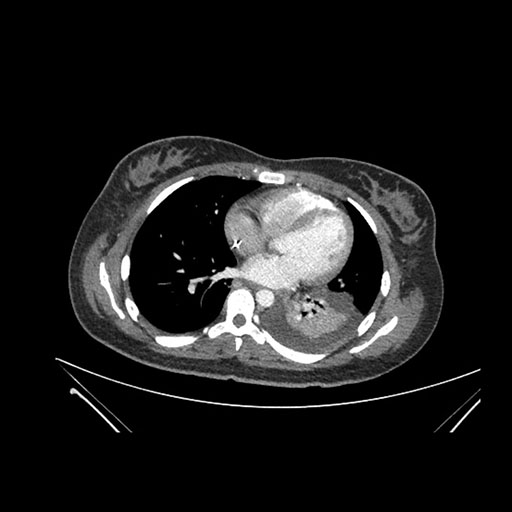

Imaging Analysis

Look through the patient's CT scan to identify any areas of concern for the necessary procedure.

Coronal Arterial